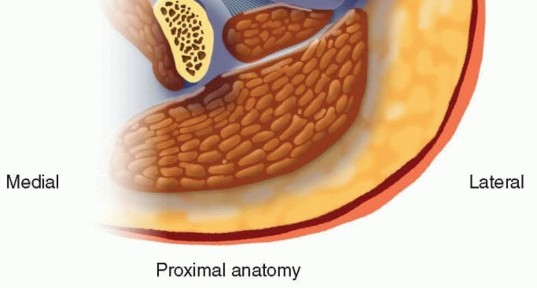

Classifications and Relative Indications It is important to assess the extent of the fracture both proximally and distally with proper radiographs. Proximally, CT scans can supplement plain radiographs to determine fracture line extension into the peritrochanteric region and to check for occult femoral neck fractures. Distally, CT imaging is helpful to assess intra-articular extension and to check for coronal plane fractures. 17 All femoral shaft fractures, as classified by the Winquist system, 33 are technically suitable for retrograde femoral nailing ( FIG 3).  ---

---  FIG 3 • Winquist femoral shaft fracture classification system.33 All fracture patterns in this system are amenable to retrograde femoral nailing.

FIG 3 • Winquist femoral shaft fracture classification system.33 All fracture patterns in this system are amenable to retrograde femoral nailing.